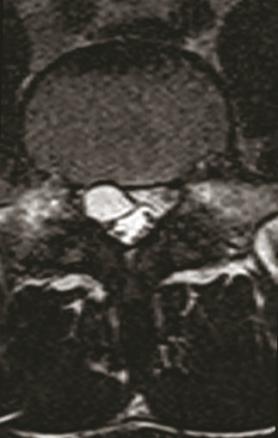

L’IRM du rachis lombaire obtenue une semaine plus tard retrouve une formation kystique développée en postéro-latéral droit du corps vertébral de L5 venant comprimer la racine L5 droite et affleurant la racine S1 droite à son émergence, évocatrice d’un kyste arthrosynovial extramédullaire et extradural (photos).